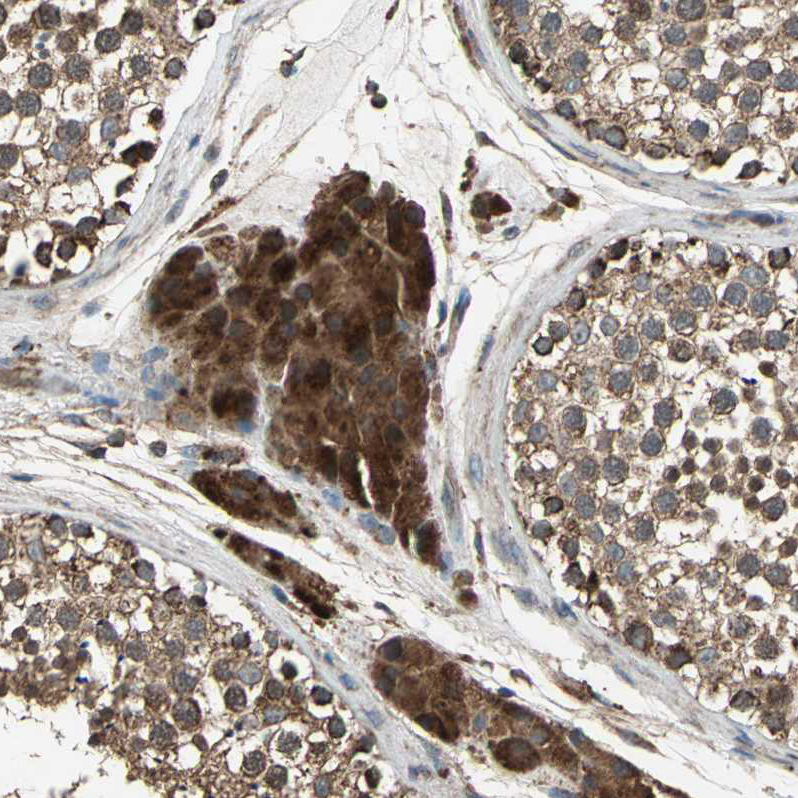

Immunohistochemical staining of human testis shows strong granular cytoplasmic positivity in Leydig cells.